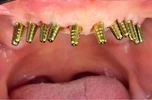

Implant tedavisi